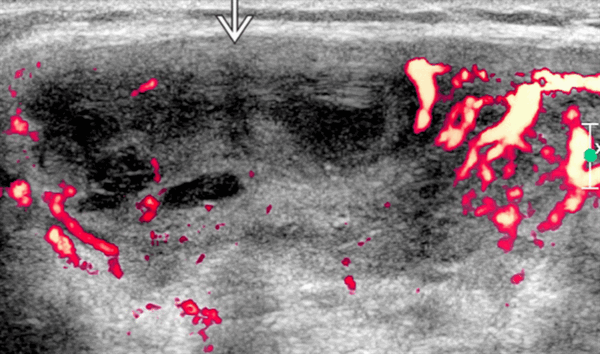

- Очаговая лимфоматозная опухоль или узел. Псевдокистозный вид с задним усилением. Четко очерченный, солидный, гипоэхогенный, гетерогенный, некальцинированный, одиночный / множественный, односторонний / двусторонний узел. Может быть диффузное вовлечение. Гипоэхогенная округлая железа с неоднородным рисунком эхоструктуры. Простое увеличение щитовидной железы, минимальное изменение картины эхоструктуры (часто отсутствует). Наличие смежных лимфатических узлов и фоновом тиреоидите Хошимото может быть только ключом к диагностике

- Фокальная лимфоматозная опухоль или узел, который имеет псевдокистозный вид с задним усилением. Хорошо очерченный, солидный, гипоэхогенный, гетерогенный, некальцинированный, одиночный / множественный, односторонний / двусторонний

- Диффузное поражение: гипоэхогенная округлая железа с неоднородным рисунком эхоструктуры. Простое увеличение щитовидной железы, минимальное изменение картины эха (часто отсутствует). Наличие смежных лимфатических узлов и фонового ТХ может быть только ключом к диагностике

- Лимфаденопатия: ретикулярная или псевдокистная картина эхоструктуры лимфоузлов. Обычно множественные лимфатические узлы ± двустороннее вовлечение на УЗИ, которые всегда солидные, а некроз не характерен. Изменения лимфоузлов вызывают масс-эффект на соседние сосуды, но не проникают в сонную или яремную вену

Рекомендации по визуализации. Лучший инструмент для обработки изображений - это ультразвуковое исследование. НХЛ щитовидной железы часто выявляют или подозревают при обычном серийном наблюдении тиреоидита Хошимото на УЗИ. Развитие очаговых гипоэхогенных узлов или плохо определенных гипоэхогенных зон у пациентов с ТХ является подозрительным для НХЛ. Наличие лимфомных узлов на УЗИ при обследовании пациента с ТХ должно вызывать подозрения на НХЛ щитовидной железы. Направленная на УЗИ биопсию узлов щитовидной железы и шеи помогает подтвердить диагноз. КТ шеи, груди, живота и таза требуется для постановки, когда диагноз известен

На что обратить внимание. Ранее было описано, что лимфоматозные узлы и лимфоузлы имеют псевдосолидную форму: анэхогенные с задним усилением. У современных преобразователей такой вид встречается редко, и внутренняя солидная природа четко идентифицируется. Лимфоматозные узлы имеют сетчатый вид на современных преобразователях высокого разрешения.